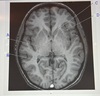

10

Q

A. Lateral ventricle

B. Insula

C. Cingulate gyrus

D.Parahippocampal gyrus

A